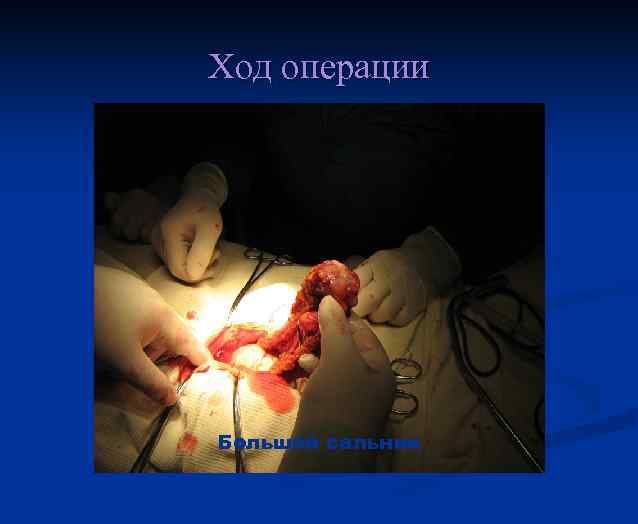

Ход операции Большой сальник

Ход операции Большой сальник